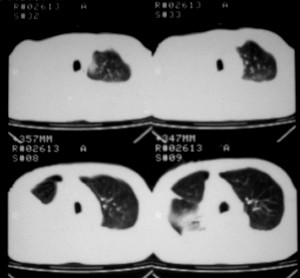

m ,60岁,右上肺ca术后一月。

右侧肺癌术后:肝内可见多个大小不等的低密度结节影。腹腔及双侧胸腔大量积液。考虑:肺癌并胸膜及肝脏转移。

纵隔淋巴结增大,双侧胸水。考虑术后残留,而非复发。

腹水,肝及右肾多发低密度影。考虑转移。

肝及右肾转移瘤,双侧胸水